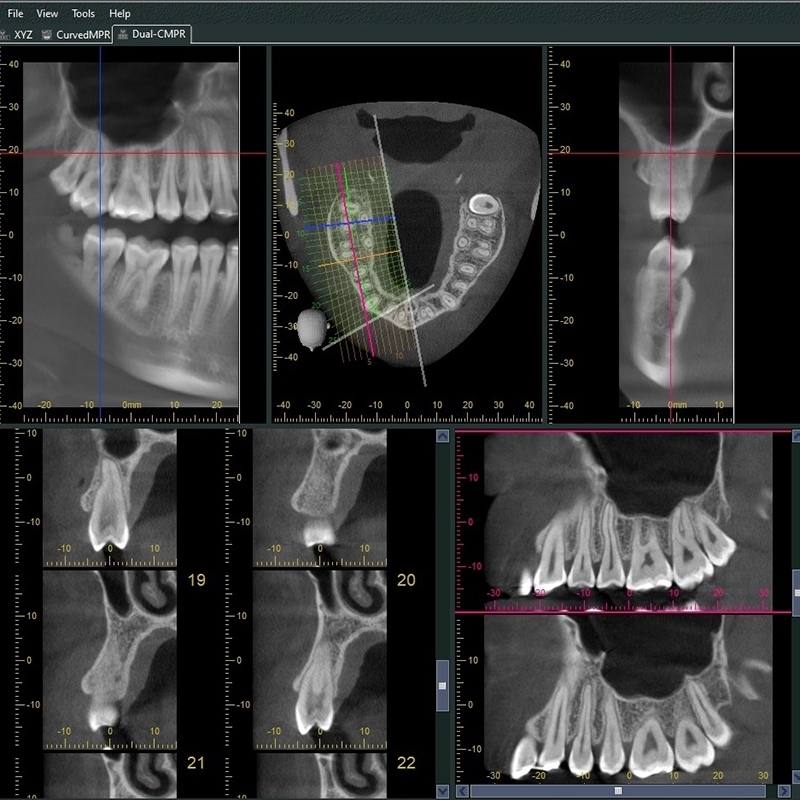

3 VERAVIEWEPOCS (X700) 3D R100 P - 1717

Information / DémonstrationPanoramique 3D - FOVs Up To: 100 x 80mm

(R100) M

Ø 40 x H 40, Ø 40 x H 80

Ø 80 x H 40, Ø 80 x H 50, Ø 80 x H 80

R 100 x H 40, R 100 x H 50, R 100 x H 80

Veraviewepocs (X700) R100 3D